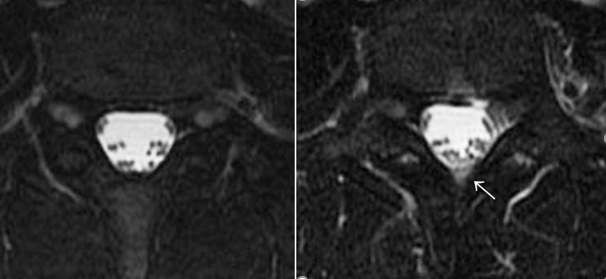

脊髄MRI(T2強調脂肪抑制像)

第4腰椎付近

左:腰椎穿刺前

右:腰椎穿刺後

矢印:iFDSS 硬膜外水信号

したがって、このiFDSSが腰椎穿刺を行う前の脊髄MRIにて観察された場合には、硬膜外の水信号すなわち髄液漏出を考えるという考察が行われた。